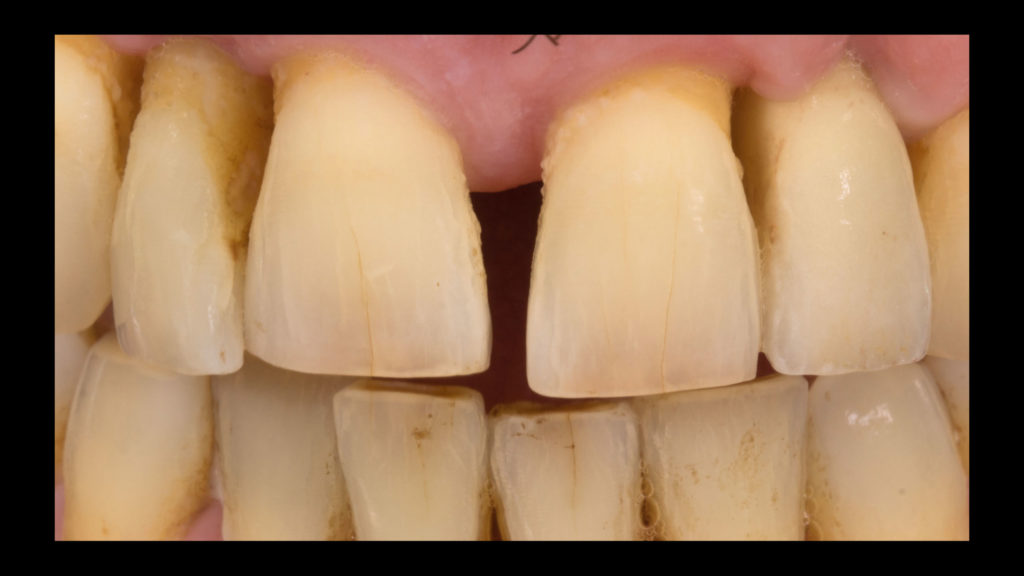

Die Implantatkrone sollte metallkeramisch gelöst werden, was wiederum bedeutete, dass für die entsprechend designte Implantatkrone ein CAD/CAM-gestützt gefertigtes Abutment (vorgefertigt, Schweden & Martina) mit einer Metallkeramik (Ceramco 3, Dentsply Sirona) verblendet werden musste. Es wurde eine zementierte Lösung gewählt, weshalb es keinen Schraubenkanal gab und somit keine Probleme mit dessen Austritt gelöst werden mussten. In den Abbildungen 6a und 6b sind die DSLR-Aufnahmen des Behandlers dargestellt. Die Referenzfarbmuster vermitteln die ungefähre Zahnfarbe, aber nicht alle Informationen und Merkmale, die für die Rekonstruktion des natürlichen Zahns vonnöten sind. Indem man die Belichtung reduziert und den Kontrast sowie die Brillanz in einem Bildbearbeitungsprogramm wie Lightroom (Adobe) erhöht, lässt sich die Histoanatomie des natürlichen Zahns besser darstellen (Abb. 6c).

Auf Wunsch des Patienten sollte der zu rekonstruierende laterale Schneidezahn die Charakteristika des mittleren Inzisiven 21, also seines direkten Nachbarzahns aufweisen. Normalerweise hätte man sich an dem noch verbliebenen lateralen Schneidezahn im ersten Quadranten orientiert, doch leider war auch dessen Zustand nicht ideal, sodass auch dieser in Bälde rekonstruiert werden sollte (Abb. 7a und b). Bei der eingehenden Betrachtung des Zahns 21 stellten wir zwar eine gewisse Ähnlichkeit mit den vom Zahnarzt gewählten Farbmusterzähnen fest, erkannten aber auch relevante Unterschiede. Aus diesem Grund starteten wir die laborseitige Analyse mit polarisierten Aufnahmen (Abb. 8a und b). Da der Patient 49 Jahre alt war, suchten wir gezielt nach charakteristischen Merkmalen natürlicher älterer Zähne und und wurden auch fündig.

Merkmale älterer Zähne

- Das Dentin junger Zähne ist von gelblich-weißer Farbe mit hohem Helligkeitswert (Value). Mit dem Alter nimmt die Helligkeit ab und das Dentin verfärbt sich dunkel-gelblich-braun.

- Die Transluzenz der Schmelzschicht nimmt zu, weshalb Dentin- und Schmelz-Dentin-Grenze stärker durchscheinen und eine chromatischere Farbwirkung entsteht. Gleichzeitig ändert sich auch der Opaleszenz-Effekt – von einer eher hellblauen, opakeren Farbe eines jungen Zahns hin zu einer dunkelroten Farbe mit hoher Transluzenz.

- Diese Farbveränderung führt bei „alten“ Zähnen zu einem dunkleren Farbton und einem geringeren Helligkeitswert, gleichzeitig aber auch zu einer Erhöhung der Farbsättigung.

- Das inzisale Drittel ist abradiert, wodurch das visuelle Merkmal eines „alten“ Zahns zusätzlich verstärkt wird. Besonders deutlich wird das in diesem Fall anhand des Gipsmodells (Abb. 9a).

- Durch Abrasion und Attrition wird die Oberfläche inzisal abgeschmirgelt. Zusätzlich entstehen Mikrorisse, aber auch Vertiefungen (Abb. 9b und c), in denen sich Verfärbungen ablagern und Konkremente anlagern – es entstehen charakteristische Verfärbungen. Und auch in den interproximalen Bereichen treten Verfärbungen stärker hervor, da sie sich schwieriger reinigen lassen.

- In einigen Fällen kann exponiertes, besonders opakes Dentin im abradierten Inzisalbereich oder an abradierten Höckern beobachtet werden.